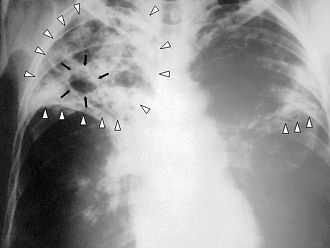

Припомняме, че по програма „Подобряване на устойчивостта на Националната програма по туберкулоза“ беше постигнато трайно двукратно намаляване на заболеваемостта от туберкулоза от 38 на 100 000 през 2008 г. до 18,4 на 100 000 през 2018 г. В абсолютни цифри броят на заболелите от туберкулоза е намалял от 3 150 през 2008 г. на 1 358 през 2018 г.